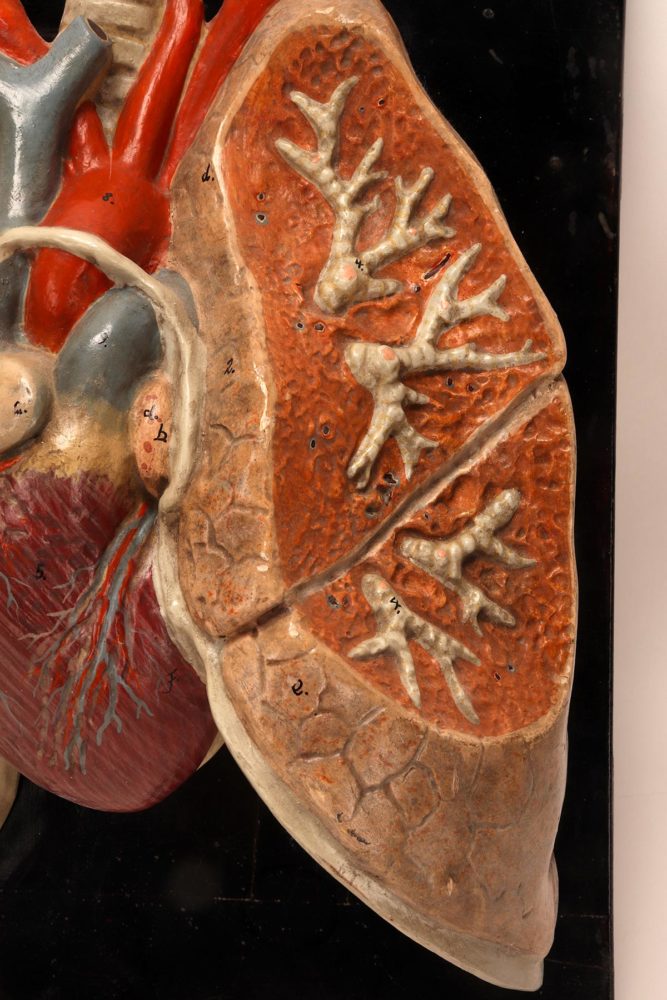

Anatomical model for class of the lungs and heart, Germany 1920.

Rare anatomical model for class, depicting human lungs and heart, made out of painted plaster, mounted on a black fruit wooden base. By Louis M. Meusel, Germany circa 1920.